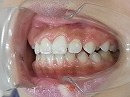

今回の症例写真は

治療が比較的困難な 出っ歯<下顎後退症> の改善症例です。

期間は1年6カ月で治療方法は独自の方法です。

この状態で大人になってしまうと

顎の調子が悪くなったり<顎関節症>

いびき<無呼吸症候群>

などの原因になってしまう事もあります。